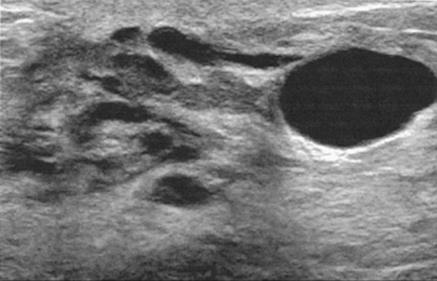

18. The mass in Fig. 10–21 is best described as:

(A) round

(B) circumscribed

(C) posteriorly enhancing

(D) spiculated

FIGURE 10–21.

19. In Fig. 10–21, what structure is the arrow pointing to?

(A) Cooper’s ligaments

(B) pectoralis muscle

(C) fibroglandular tissue

(D) skin

20. This image in Fig. 10–22 demonstrates: